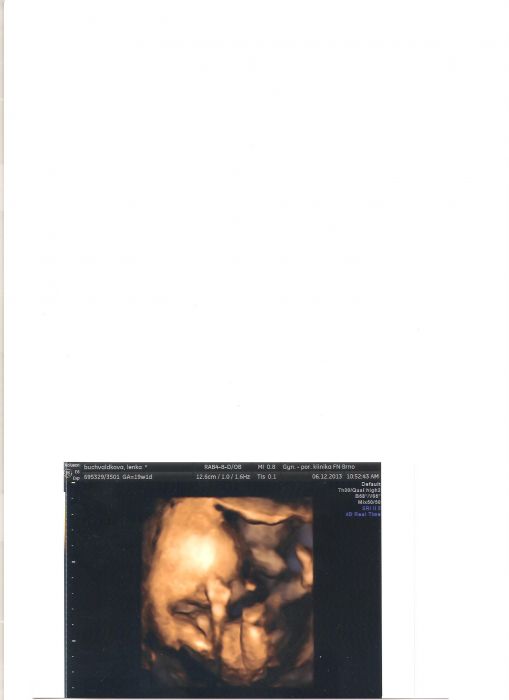

To jsem taky slyšela, že holčička je jistá :-) no uvidíme...všichni co viděli utzv. tak vidí kluka...jen já i když mám oči jako šnek nevidím nic :-) je to z 19. týdne.

[430786] já tam teda "kouličky" nevidím

, tak bych věřila té holčičce...

Tak to my zase museli pořídit všechno znova. Dcera má 22 a tak doma už nic nezbylo. Zrovna dneska jsem sehnala od známé polohovací lehátko od Chicco za 400. A taky jsme ve Svitavách našli obchod s nádhernýma věcma za super ceny. Myslím, že to vozí z Polska. Už nám chybí jen kočárek a postýlka s přebalovacím pultem. Byli jsme kouknout na kočárky a asi z 50- ti se mi líbil jen jeden. Takže to bude asi trošku oříšek. 6.2. jdu zase na utzv. tak jsem zvědavá. Milule se Šmidlovi nechtělo fotit. Pořád si dávalo ruce před obličej :-)